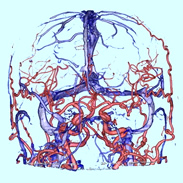

MRI検査

MRIはMagnetic Resonance Imaging (磁気共鳴画像)の略で、強力な磁石の力で体の内部を画像化する装置です。一般撮影検査やX線CT検査などと異なり、放射線を使用しないため被ばくがなく、何回検査をしても体に悪い影響はありません。ただし道路工事をしているような大きな音がしたり、検査室内に金属が持ち込めない等の制限があります。けがの治療などで体内に金属を入れている方は事前にご相談ください。

当院では3.0テスラMRI装置と1.5テスラMRI装置が稼働しています。

- ・脳神経外科領域

- MRIが最も得意とする部位で、頭の血管の描出や脳梗塞、認知症の検査が可能です。予防医学センターでは脳ドックも行っております。